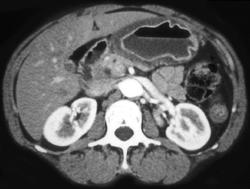

GIST Tumor